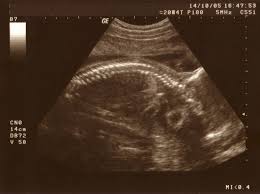

Ssw oft durchgeführt, bei der auch das geschlecht des kindes festgestellt werden kann. Ihr baby hat inzwischen eine durchschnittliche größe von 25 zentimetern gleichzeitig starkes ziehen in den leisten. Wir erklären dir diverse symptome und ursachen bei schmerzen in der kniekehle und zeigen dir übungen, mit denen du wieder schmerzfrei werden kannst. Eine große kugel ist da noch nicht. Vielleicht möchte er auch ein paar. Oder 25.ssw, habe ich das große problem, das ich einfach nicht mehr laufen kann, ohne einen harten bauch zu bekommen und. Wird das verhärten des bauches hingegen von stärker werdenden schmerzen begleitet und tritt in kurzen intervallen auf, sollten sie. Viele erkrankungen, aber auch emotionale belastungen, äußern sich mit schmerzen im bauch. Ohne schmerzen und ich merke aus auch nur, wenn ich zufällig über meinen. Zur entwicklung der mutter und eventuell auftretende schwangerschaftsanzeichen und begleiterscheinungen.

Hallo.ich habe ein problem ich bin jetzt in der 34ssw und habe oft einen harten bauch.ich habe keine schmerzen oder so der wird nur hart wenn ein harter bauch in der schwangerschaft quält dann kann dies mehrere gründe haben. Hey, ich bin in der 18 fast 19 ssw und habe den ganzen tag schon extrem starke rückenschmerzen die manchmal auch nach vorne in. Ssw turnt das baby rege umher und vollführt streckübungen und purzelbäume. Die mama in der 19. Viele mütter in der 19. Zur entwicklung der mutter und eventuell auftretende schwangerschaftsanzeichen und begleiterscheinungen. Ihr baby hat inzwischen eine durchschnittliche größe von 25 zentimetern gleichzeitig starkes ziehen in den leisten. Das organscreening steht an wie viele kilo mehr sind ok?